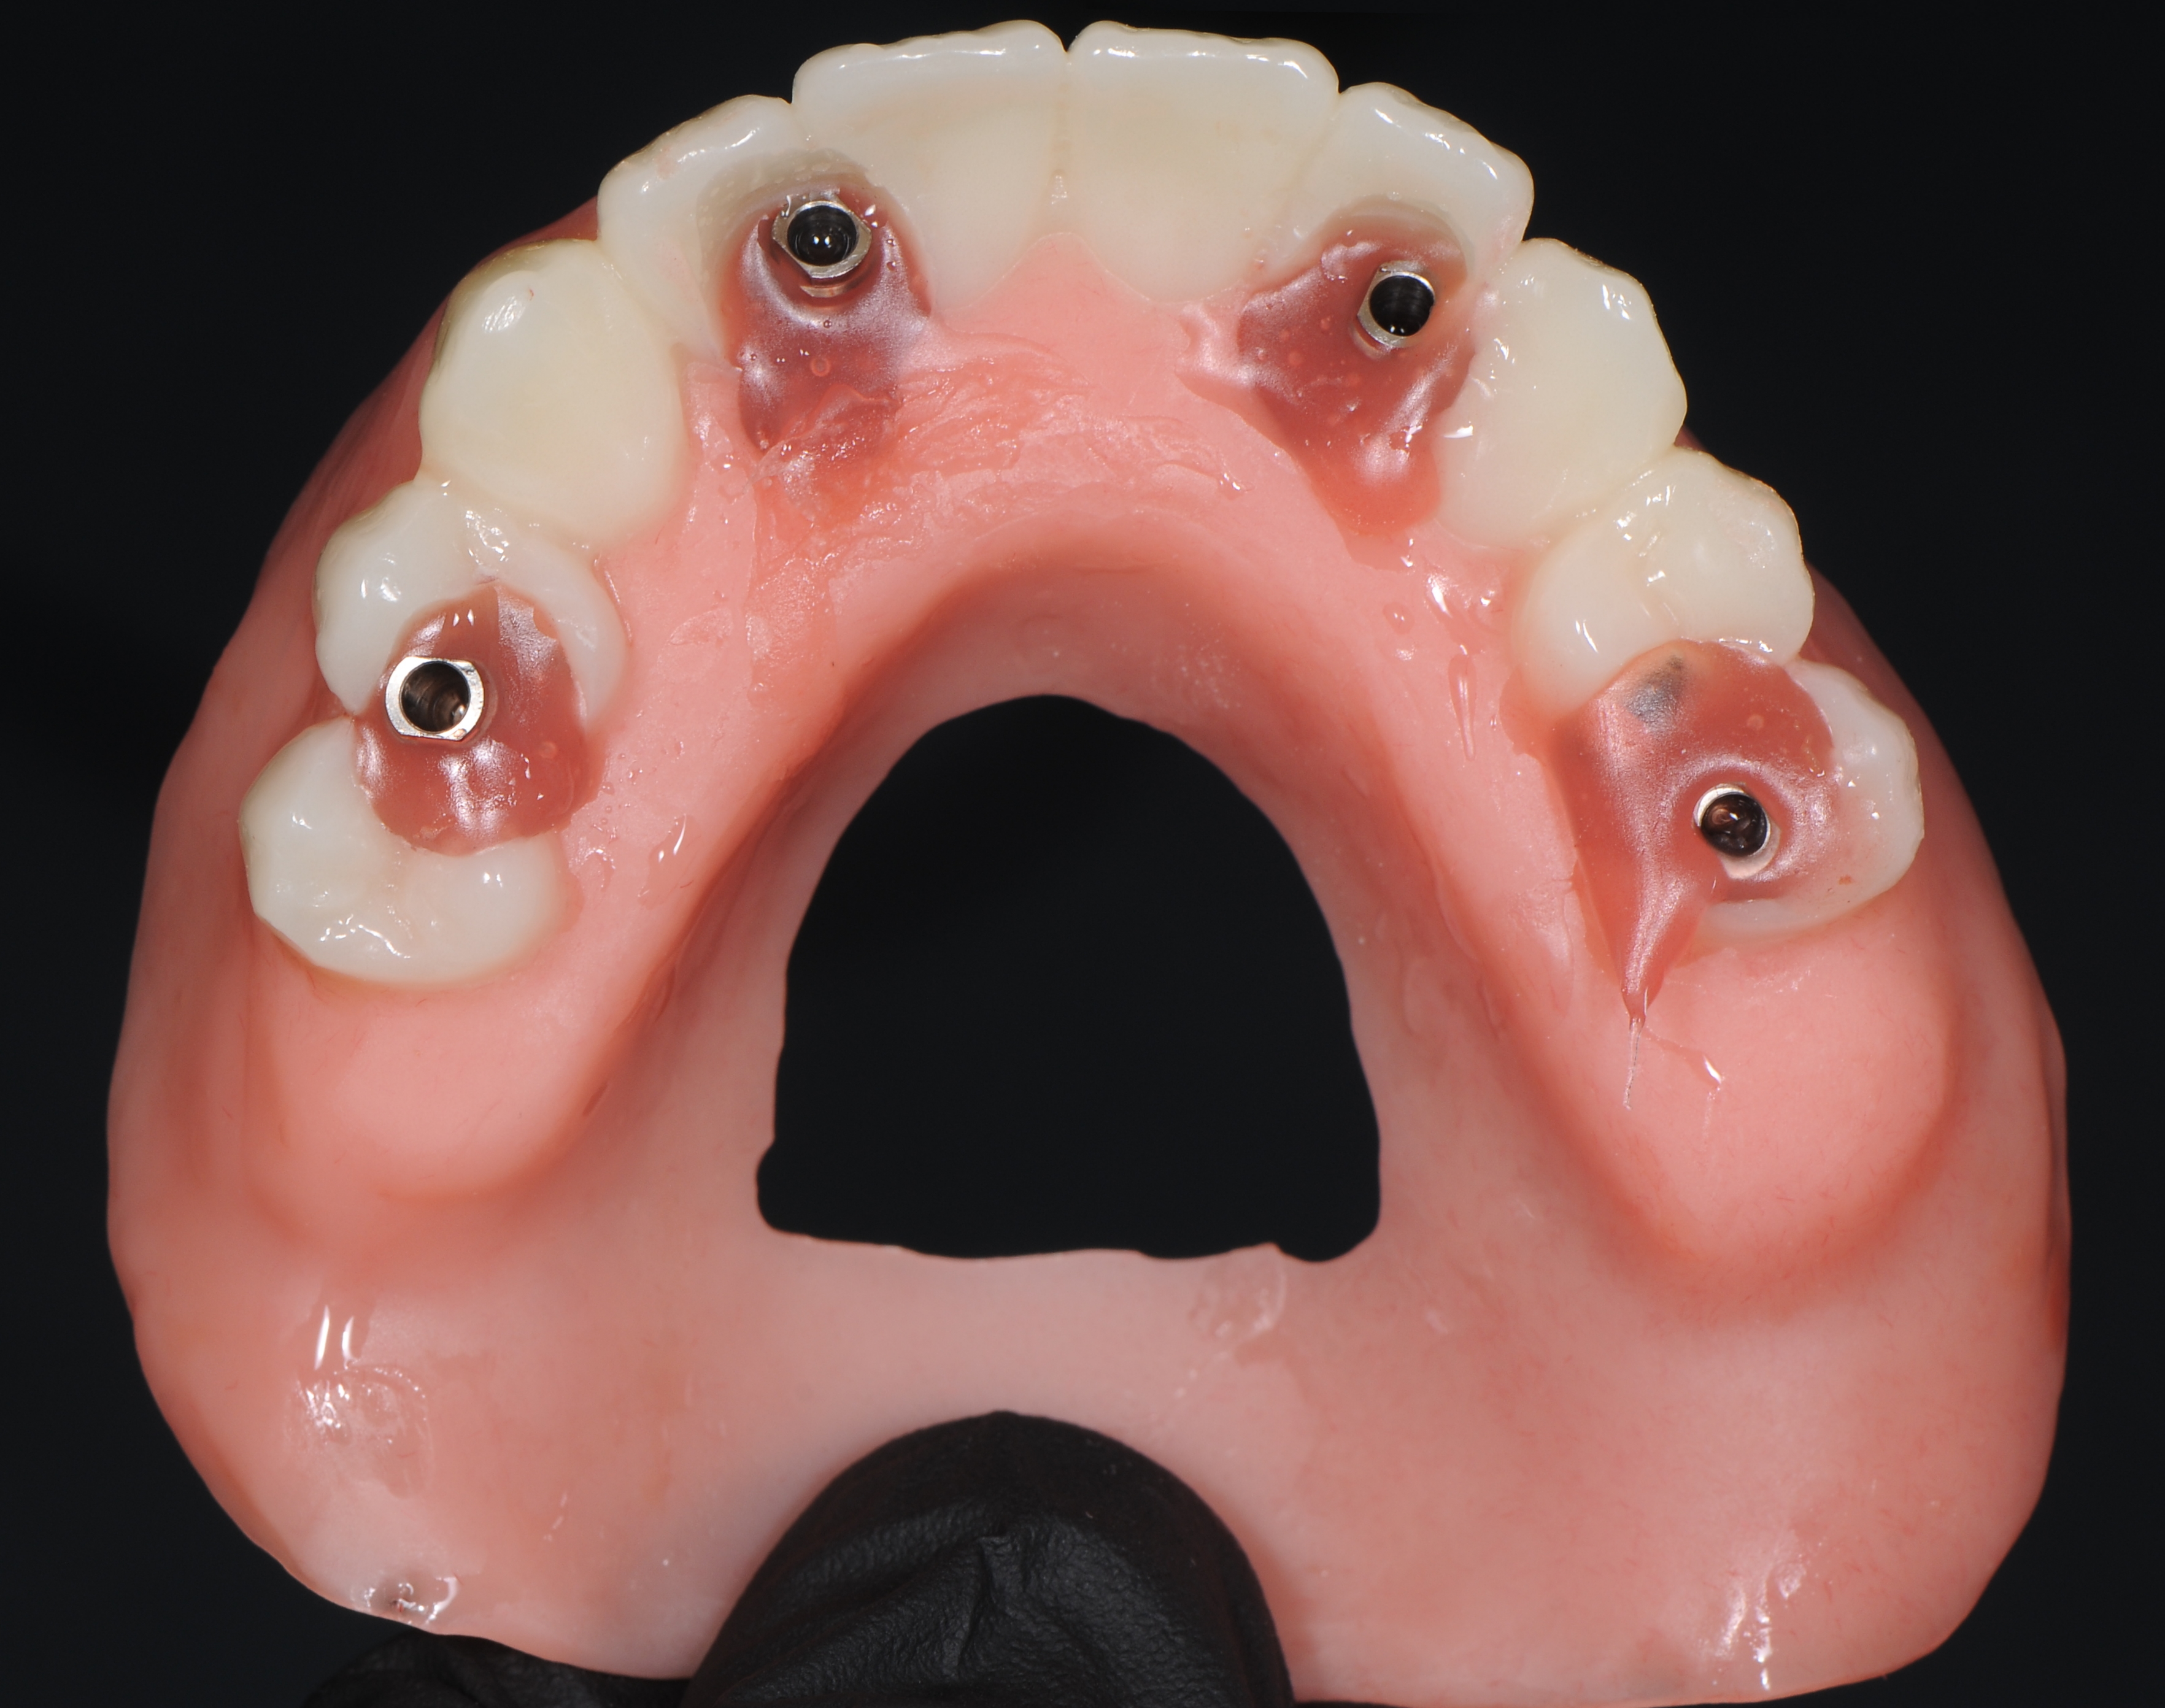

После полимеризации композита откручивались винты и проверялась пассивная посадка титановой балки к аналогам имплантата. Уже после этого зубной техник припасовывал акриловый протез к модели и перебазировал с пластмассой холодного отверждения на основе полиметилметакрилатов. После полимеризации протеза сошлифовали небную пластинку и излишки базиса с вестибулярной поверхности, при этом придесневая поверхность протеза оставалась относительно выпуклой или плоской , чтобы в дальнейшем не препятствовать осуществлению самостоятельной гигиене полости рта пациента (рис.34,35).

Фиксация временного протеза к абатментам в полости рта пациента с усилием 15 N/см2 окклюзионные контакты только в переднем участке (от клыка до клыка) (рис. 36,37).